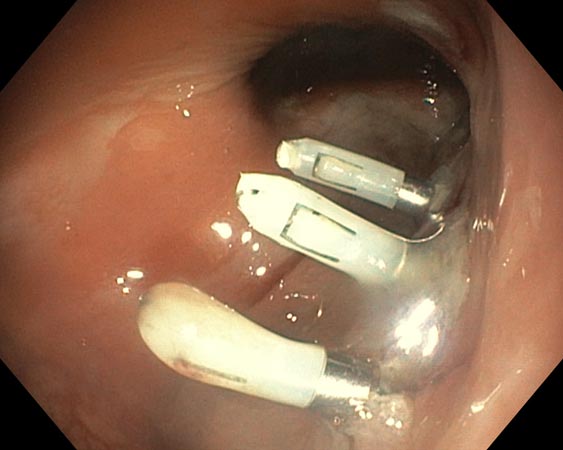

Проводили удаление образования единым блоком для проведения патоморфологического исследования. В случае моноблочной и фрагментарной резекции образования использовали диатермическую петлю SD-210U-25. Сведение краёв клипсами выполняли только после диссекции подслизистых образований (рис. 3–6).

Рис. 6. Клипирование дефекта

Возникшие в ходе 8 (38,1%) операций интраоперационные осложнения устранены эндоскопически. Серьёзное осложнение с нарушением герметичности стенки толстой кишки в ходе диссекции произошло у пациентки с латерально распространяющейся опухолью сигмовидной кишки. Перфоративное отверстие диаметром 0,3 см в зоне умеренного фиброза (F1) устранено эндоскопически сведением краёв дефекта клипсами в течение 5 мин с момента его обнаружения (рис. 7, 8).

Рис. 7. Перфоративное отверстие

Рис. 8. Клипирование перфорации